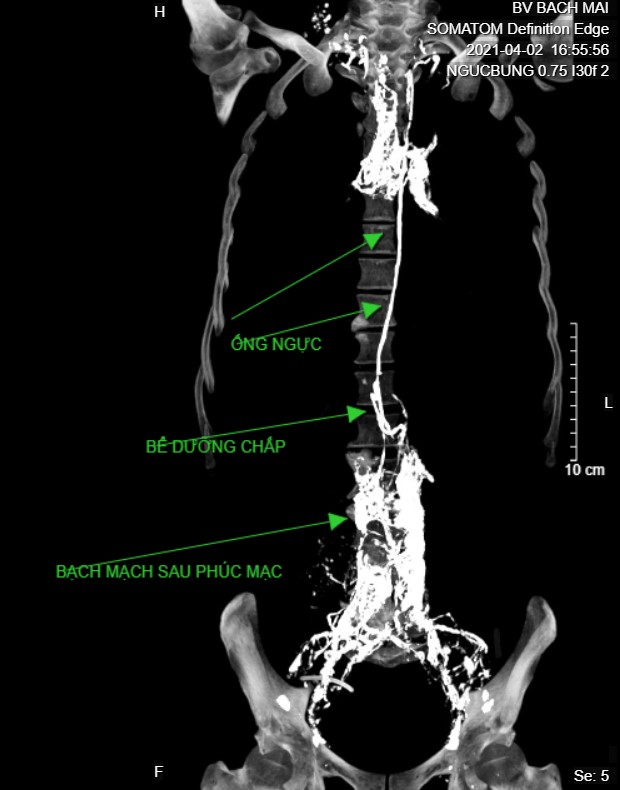

Ảnh 4. Chụp CT sau chụp DSA cùng bệnh nhân, thấy bạch mạch sau phúc mạc, bể dưỡng chấp và ống ngực. Lipiodol trong bạch mạch trung thất